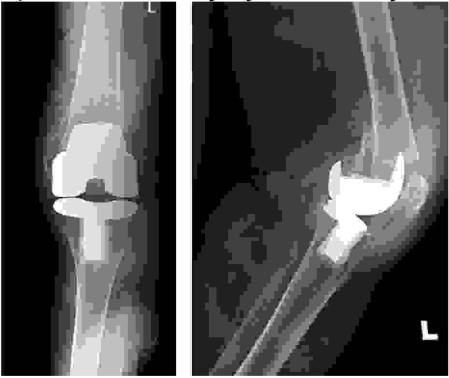

Złamanie końca bliższego goleni u 45-letniego mężczyzny o morfologii jak na przedstawionych RTG i CT. Wskaż, które postępowanie jest najlepsze: